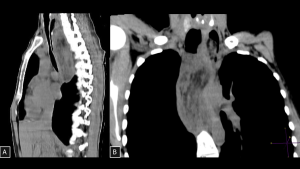

Fig 15: Case 16 - Liposarcoma:

Panel A (coronal CT image) demonstrates a large heterogeneous solid mass occupying the middle and lower portions of the left hemithorax, with features suggestive of posterior mediastinal origin. Panel B (axial CT image) shows the lesion containing mixed components of macroscopic fat and soft-tissue attenuation, causing rightward displacement of the esophagus and close contact with the descending thoracic aorta and left atrium, imaging features consistent with mediastinal liposarcoma.

SYSTEMATIC APPROACH: 1. Age: Adults. | 2. Morphology: Heterogeneous mass with areas of macroscopic fat and solid components. | 3. Enhancement: Heterogeneous (solid areas). | 4. Relevant Anatomical Relationships: Invasive behavior; direct invasion of adjacent structures is common.

Fig 16: Case 17 – Paravertebral hematoma in trauma:

A 27-year-old patient who sustained a 10-meter fall presented with multiple vertebral body fractures from T8 to T11 (arrows in C) and a large paravertebral mediastinal hematoma extending from T5 to T11 (B), causing anterior displacement of visceral mediastinal structures. An arterial focus of active bleeding was identified (arrows in A).

SYSTEMATIC APPROACH: 1. Age: Any (Trauma/Coagulopathy). | 2. Morphology: High attenuation on CT (50–70 HU) in acute phase. | 3. Enhancement: None (except active extravasation). | 4. Relevant Anatomical Relationships: Paravertebral; displaces mediastinal pleura laterally (extra-pleural sign).